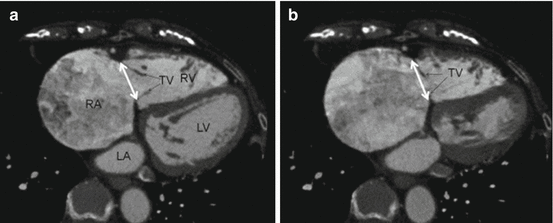

Fig. 9.1

Arrhythmogenic RV dysplasia on cardiac CT. Reprinted with permission from “Value of Cardiac CT in Patients with Heart Failure” by Deepa Mangalat et al., J Curr Cardiovasc Imaging Rep. 2009 Dec; 2(6): 410–417. Springer Science and Business Media, LLC 2009